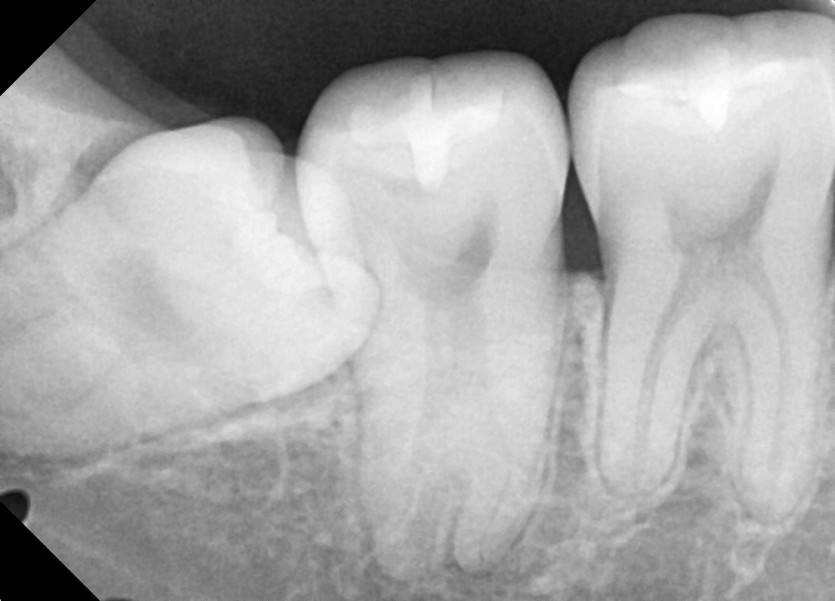

#48 사랑니 발치

구강 외과 전문의가 당일 발치했습니다.